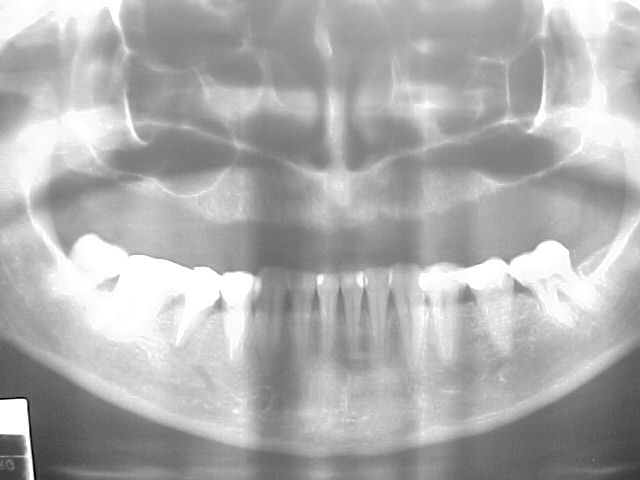

RX panorâmico anterior ao tratamento

Diagnóstico preliminar das principais ocorrências: Prótese total na maxila em articulação com dentição natural inferior, apresentando acentuado trespasse horizontal (mordida profunda) e inclinações linguais generalizadas, com ausência do primeiro molar inferior esquerdo.

Confirmação da inclinação lingual generalizada em todos os elementos dentários